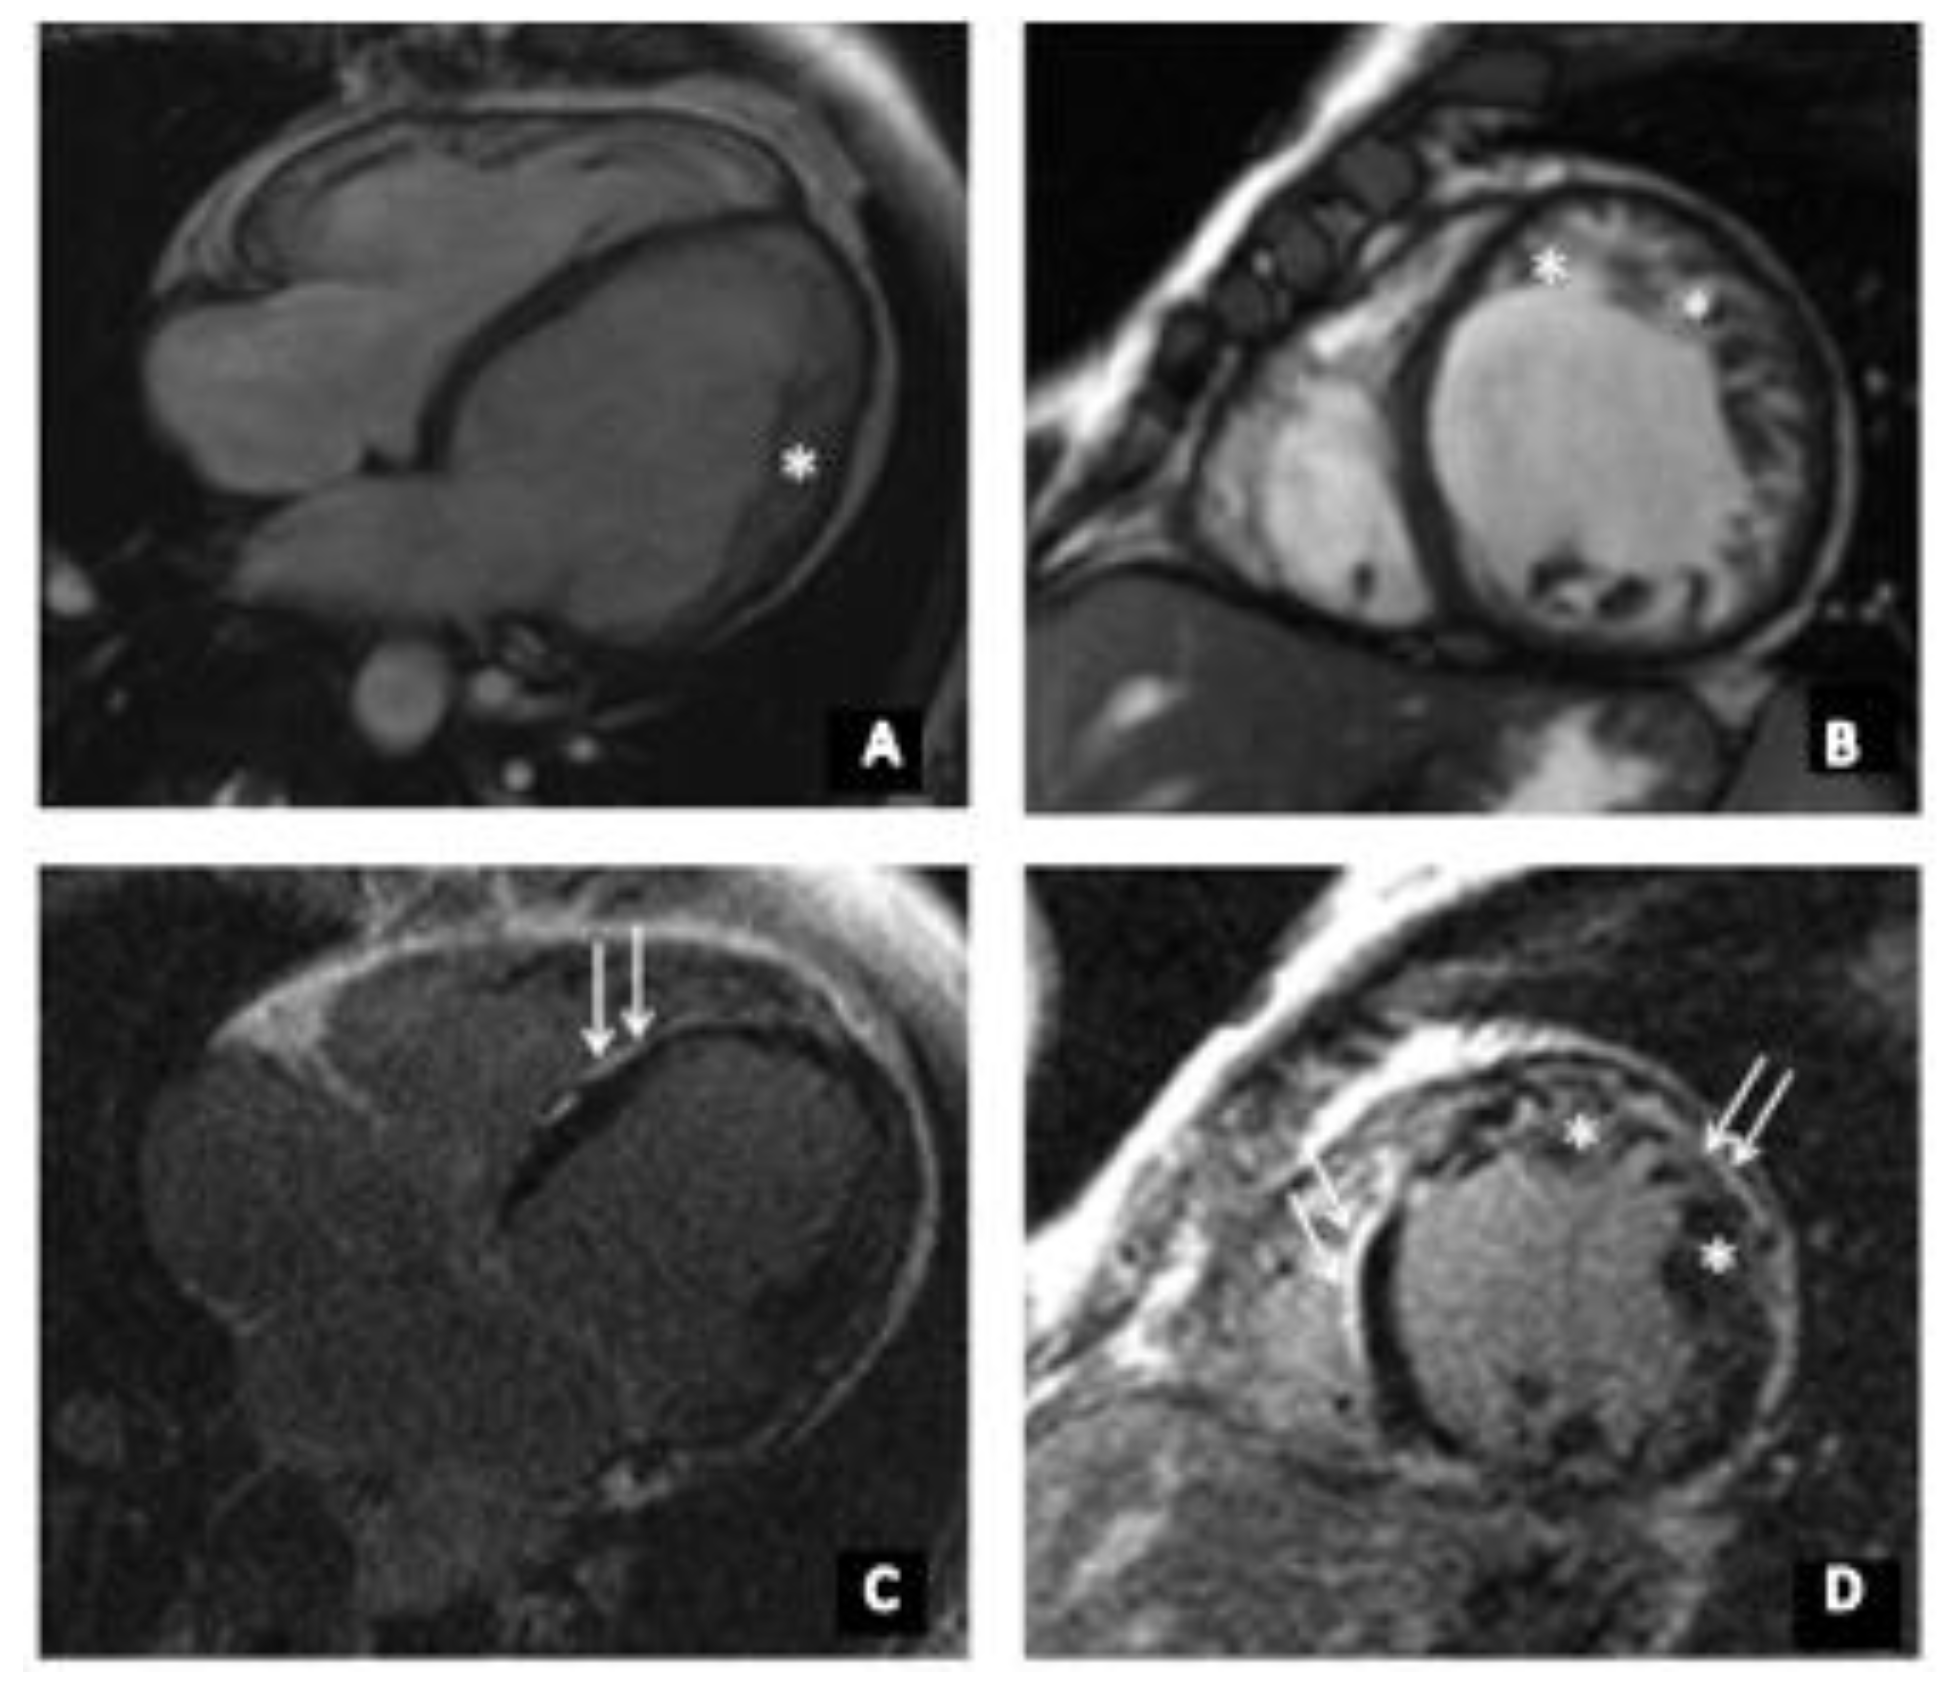

2.2. Cardiac Magnetic Resonance Imaging